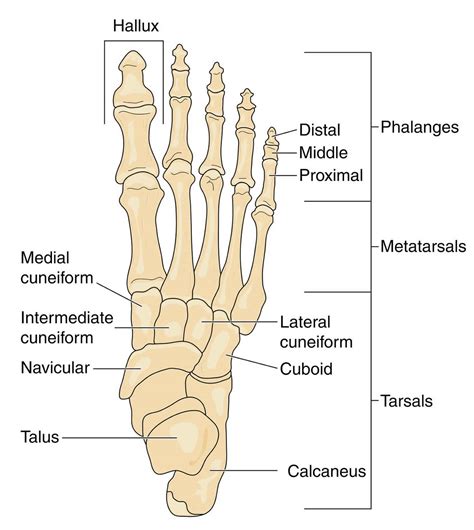

The scaphoid is a peanut-shaped bone located on the thumb side of your wrist, just above the radius. It plays a significant role in how your wrist moves, acting as a bridge between the two rows of carpal bones. What makes this injury particularly tricky is the bone's unique blood supply. Blood flows into the scaphoid from the distal end toward the proximal end. When a fracture occurs, the blood supply to part of the bone can be disrupted, significantly hindering the natural healing process.